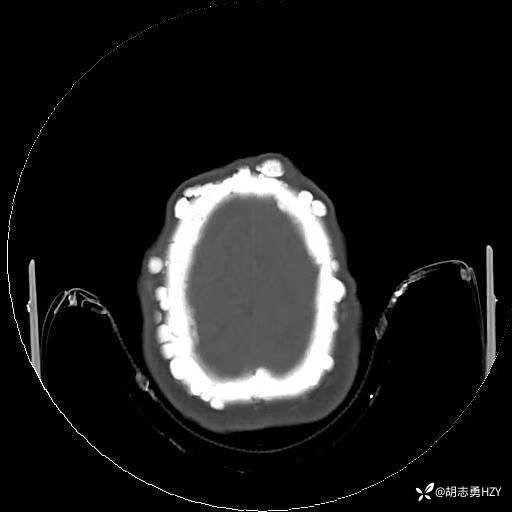

女性,45岁,家族性腺瘤性息肉病,额部顶部多发无痛性硬质包块(2025 1108)

女性,45岁,家族性腺瘤性息肉病,额部顶部多发无痛性硬质包块